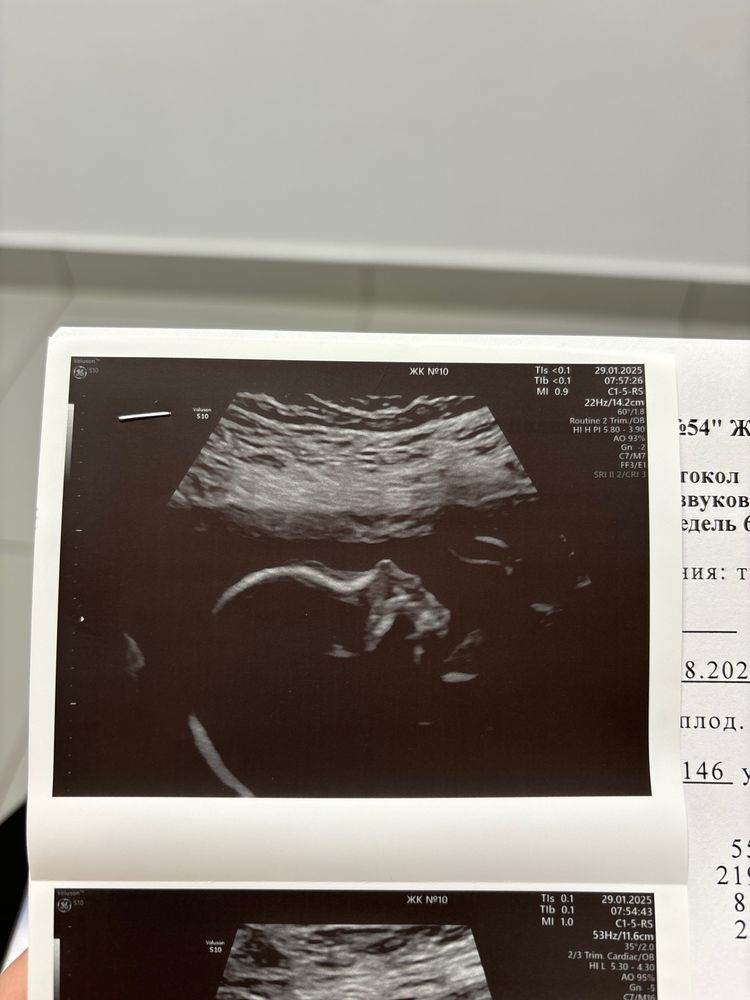

ходила смотреть вчера на нашу крошку, растем, вес уже 600 грамм, перевернулась и сидит попой теперь

надеюсь ближе к родам все-таки вернется в правильное положение 🙏🏼❤️